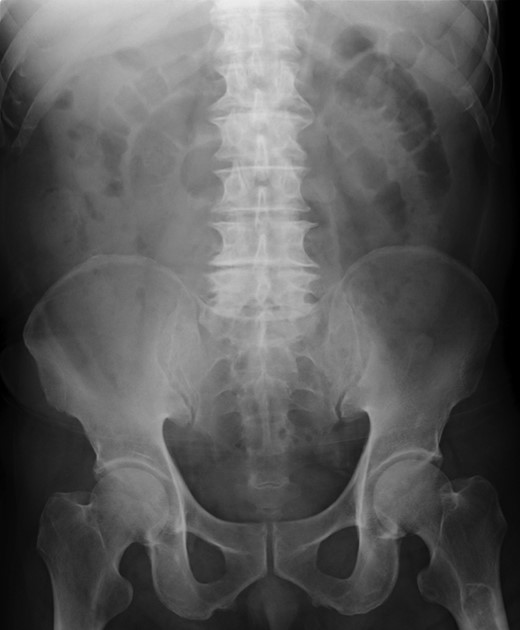

A 79-year-old man with acute abdominal pain had gone to a nearby hospital. As HPVG was detected by abdominal computed tomography (CT), he was transferred to our hospital for further examination and treatment. He had no remarkable past medical history. When he arrived at our hospital, his vital signs were relatively stable (body temperature: 37.2°C; blood pressure: 112/74 mmHg; pulse rate: 68 beats/min). However, physical examination revealed abdominal distention, rebound tenderness and abdominal guarding as signs of peritoneal irritation. The laboratory findings indicated acute inflammation (white blood cell count of 18 400/μL and Creactive protein concentration of 17.7 mg/dL), dehydration and metabolic acidosis (a level of base excess of −7.0 mmol/L). Creatine kinase was remarkably elevated (28 327 IU/L) (Table 1). Plain abdominal radiographs showed distention of the small intestine and suggested subileus (Fig. 1). Contrast-enhanced abdominal CT revealed HPVG (Fig. 2a), a contrast defect in a region of the small intestine, and a small amount of ascites around the intestine. There was no thrombus in any artery; however, the wall of the appendix was moderately thickened when we reevaluated the images retrospectively (Fig. 2b). We performed an urgent laparotomy with the diagnosis of generalized peritonitis caused by intestinal necrosis. A small amount of turbid ascites and a dilated small intestine were observed in the peritoneal cavity. Although the entirety of the small intestine and colon were explored, no intestinal ischemia was detected. Then, we found discoloration of the appendix with wall thickening. We thus made a clinical diagnosis of peritonitis caused by gangrenous appendicitis. Although the appendix wall was fragile, no macroscopic perforation of it was observed. We performed appendectomy and abdominal drainage. Based on the pathological findings, the patient was diagnosed with gangrenous appendicitis, with no evidence of malignancy (Fig. 3). Escherichia coli was positive in the ascitic culture. After the surgery, intravenous antibiotic treatment (meropenem) was administered. The patient subsequently went into septic shock with disseminated intravascular coagulation (DIC). He was therefore admitted to the intensive care unit (ICU), where he received blood purification therapy. The CT images on Day 7 after the surgery showed that HPVG had disappeared (Fig. 4). He left the ICU 7 days after the surgery and was discharged from the hospital another 10 days later.

Abdominal CT on Day 7 after the surgery showed that HPVG had disappeared.